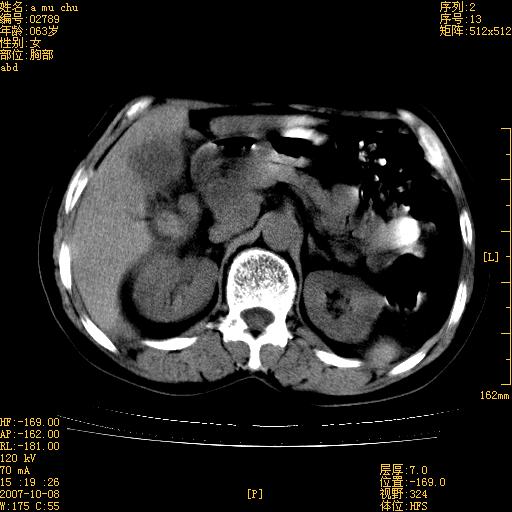

以下是引用王维浦在2007-10-17 21:02:00的发言:[br]胆囊增大,囊壁明显不规则增厚,邻近肝组织浸润,肝内外胆管无扩张。诊断:胆囊ca;[br]胰头软组织肿块影,考虑是由转移肿大的胰后淋巴结、没有肠道准备的十二指肠及胰头共同形成。[br]

以下是引用zhangzexing在2007-10-18 7:13:00的发言:[br]支持胰头占位,慢性胆囊炎. 2.肝左叶前外侧段占位,血管瘤?建议增强

以下是引用影像实习生在2007-10-17 19:49:00的发言:[br]支持胰头占位,慢性胆囊炎. 2.肝左叶前外侧段占位,血管瘤?建议增强.

以下是引用刘振江在2007-10-17 19:42:00的发言:[br]没有增强,胰头癌?胆囊及肝左叶占位?